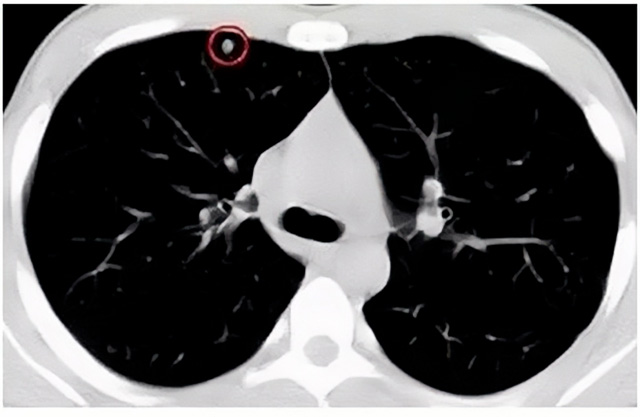

移動CT體檢車可以檢查肺結節發現早期肺癌

移動CT體檢車可以做肺部檢查。隨著多層螺旋CT肺部低劑量掃描的臨床應用,目前很多人選擇肺部CT作為常規檢查項目,較大地提高了肺結節的檢出率。如果檢查發現肺部有肺結節是磨玻璃型的,小于5mm的微小結節,大部分都是良性的。如果達到1CM以上的,很有可能有肺癌的機率。根據其內密度不同可分為磨玻璃結節、實性結節、部分實性結節。根據其大小可分為肺大結節、小結節和微小結節。如果是炎癥性肺結節,幾個月后復查有變化變小就不用做手術。如果CT再次復查結節沒有變化,沒有縮小就需要升級做病例檢查。病理檢查的確診性是最高的。是有沒患癌的標準。檢查發現早的話,規范手術治療,手術后5年的存活率很高的。肺癌這個要早發現早治療。

現在的移動CT體檢車的分辨率比X光高,CT掃描的圖像越來越薄顯像更清晰,檢查更準確。得到了普及,肺結節的測出率很高的。但是顯浩告訴大家,肺結節不等于肺癌。雖然很多是良性,但是很多肺癌都是肺結節發展來的。 必須定期檢查復查。磨玻璃結節,肺癌的機率較高。肺癌是惡性腫瘤病死率最高的。除了環境,遺傳,等因素。吸煙,從事煙霧工作行業的人員比較危險。發病比例高。肺部疾病早發現早治療,依舊是肺部疾病的治療標準。

一旦CT檢查發現肺結節,若不規律復查,檢查等同于白檢。所以在復查中,如果結節中發現有增大的趨勢,或大小發生了變化,我們必須提請注意及時治療,不要掉以輕心。移動CT體檢車的普及化,讓肺部檢查更準確更高效。發現肺結節時,及時就醫并進行專業評估是確保準確分類和采取適當措施的關鍵。